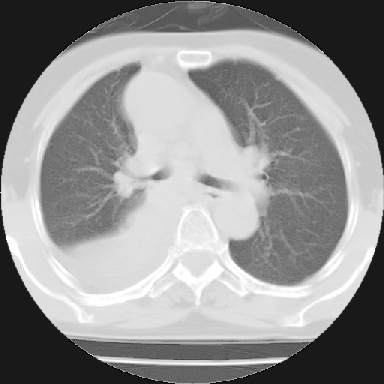

以下是引用苯小孩在2007-4-13 16:20:00的发言:[br]1、右下肺中央型肺癌并阻塞性肺不张、肺内转移、胸椎右侧附件亦有转移<横断层面第8层>.[br]2、右侧胸腔积液.

以下是引用swyyy2007在2007-4-13 15:31:00的发言:[br]右肺门下区肿块,右肺下叶支气管阻塞,右肺下叶不张,右侧大量胸腔积液,右肺中叶见结节状高密度影,边缘清,纵隔内见肿大淋巴结。首先考虑右下肺中心型肺癌伴右肺下叶不张、中叶、纵隔淋巴结转移。右侧胸腔积液。